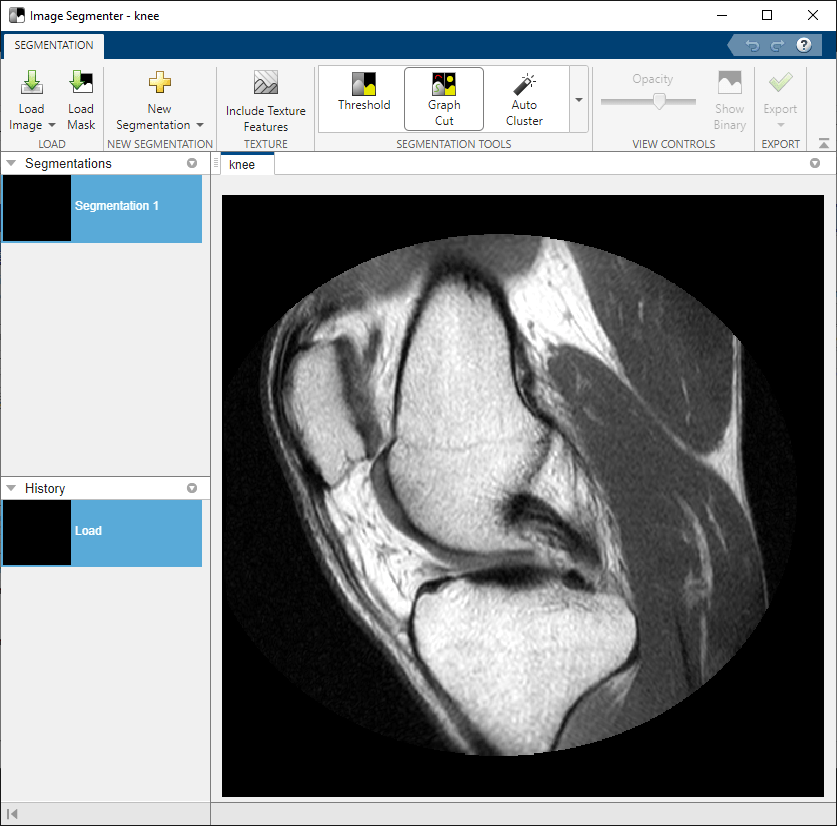

knee = mat2gray(I);Abra la app Image Segmenter desde la barra de herramientas de MATLAB®. En la pestaña Apps de la sección Image Processing and Computer Vision, haga clic en Image Segmenter

.

En la barra de herramientas de la app, haga clic en Load y, a continuación, seleccione Load image from Workspace. En el cuadro de diálogo Import from Workspace, seleccione la imagen que ha leído en el área de trabajo. Image Segmenter muestra la imagen seleccionada.

También puede abrir una imagen en la app Image Segmenter utilizando el comando imageSegmenter, tal como se muestra a continuación:

imageSegmenter(knee);